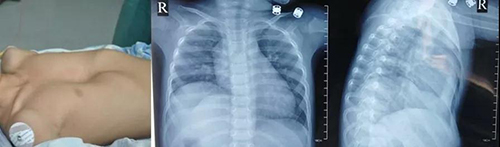

莱芜2岁患儿明明(化名)从小胸前有个巨大的凹陷。随着年龄的增长,这个“大坑”越来越大。去年的一次查体中,明明被检查出患有先天性心脏病——房间隔缺损。焦急的父母经多方打听,带孩子来到山东省立医院。经过入院后的详细检查,明明被诊断为“先天性心脏病、完全性房室间隔缺损、二尖瓣前叶裂并中度关闭不全、肺动脉高压、漏斗胸、右侧膈膨升”。

尽管幼小的明明合并多种疾病,但山东省立医院的专家团队不畏困难、精心救治。经过认真细致的术前讨论,去年6月,心外科、儿外科专家团队联合为患儿实施了手术。手术由心外科主任医师邹承伟、儿外科主任医师刘桂海主刀,心外科副主任医师张海洲、主治医师张涛为助手,主任医师许崇恩、主治医师张军负责体外循环麻,麻醉手术科密切配合。专家团队经过5个小时的奋战,顺利完成了我院首例“经右胸二尖瓣裂修补+房室间隔缺损修补+右侧膈肌折叠+漏斗胸矫治手术”。术后,经心外监护室及心外科病房护理人员的精心护理,患儿迅速恢复并于术后第7天顺利出院。

如今,手术完成已经半年,近期的随访中,我们再一次见到了明明,他胸前的“大坑”已经完全消失,先天性心脏病得到了有效的治疗,家长和孩子们都露出了幸福的笑颜。

术后7天

术后2个月

术后6个月